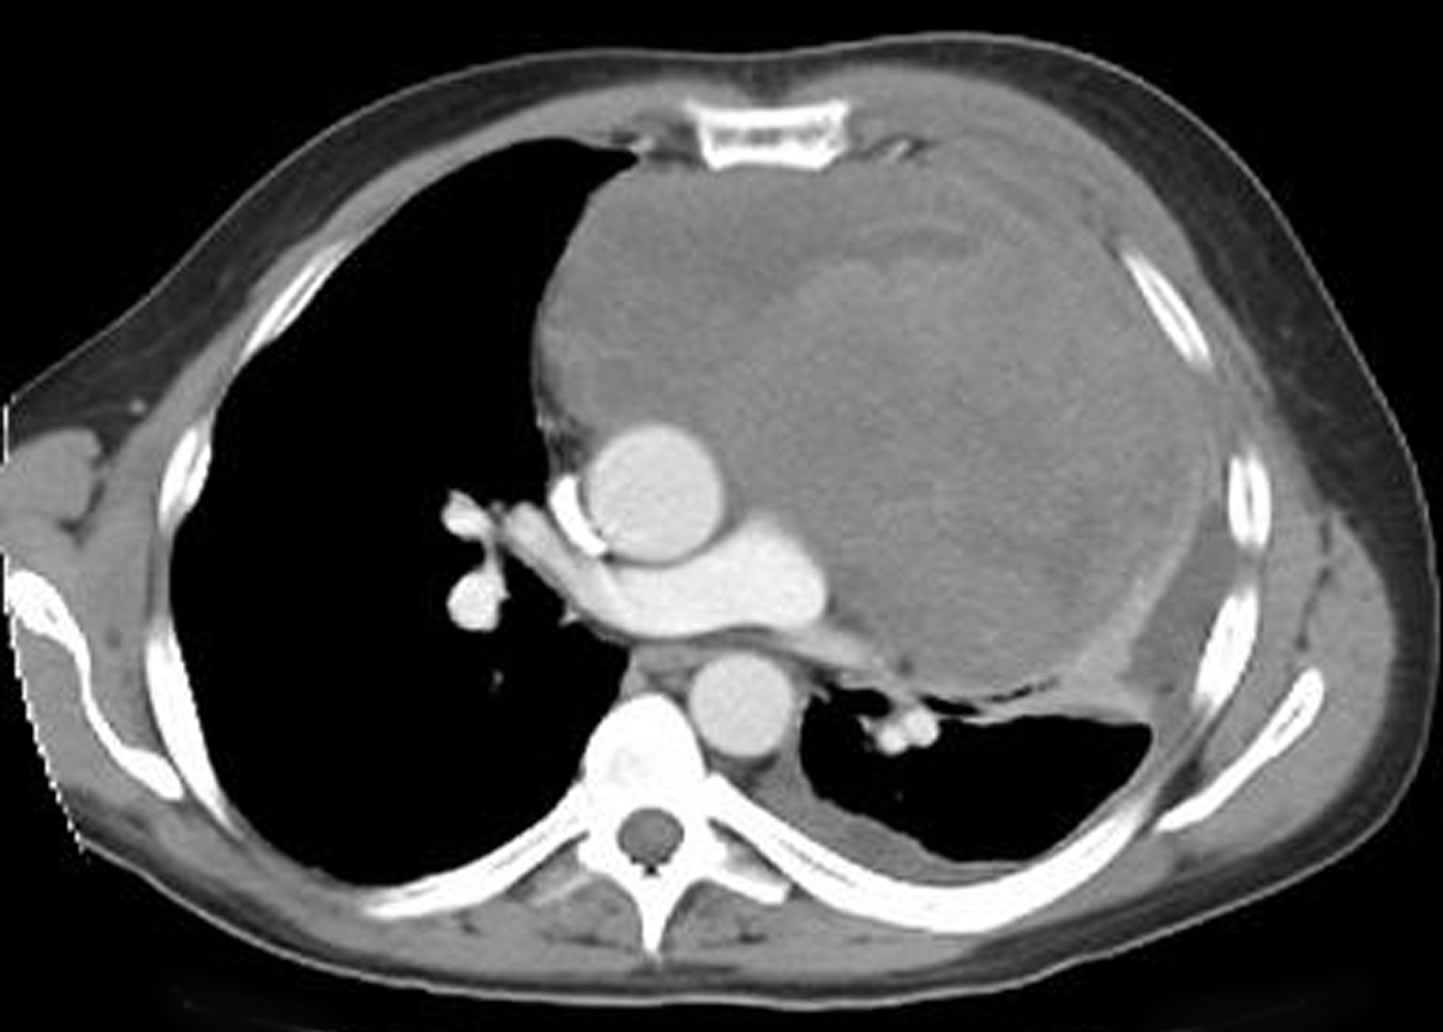

Any anterior mediastinal mass (Figures 1, 2) must be considered suspect for germ cell tumor, especially in a young male. Errors in diagnosis are not uncommon and can result in mismanagement of a potentially curable patient. All patients with an anterior mediastinal mass should have alpha-fetoprotein (AFP), β-human chorionic gonadotropin (β-HCG), and lactate dehydrogenase (LDH) levels drawn at the outset. The different types of germ cell histologies are shown in Figure 3.

Figure 2: Computed tomography of mediastinal germ cell tumor